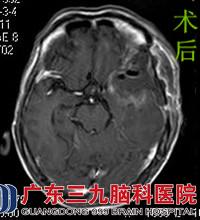

原来近日的各种症状竟是肿瘤所致。为了进一步治疗,天淑来到广东三九脑科医院综合神经外科。行头颅MR检查提示左侧额颞部示不规则团块状异常信号,大小约48.1mm×46.8mm×47.4mm。完善相关检查后,由鲁明主任主刀,在全麻下行左侧翼点入路蝶骨嵴脑膜瘤切除术,术中见肿瘤位于颞叶,质软,血供丰富,予镜下行肿瘤全切,手术顺利结束。术后天叔经治疗护理,康复出院。术后病理结果:过渡型脑膜瘤。